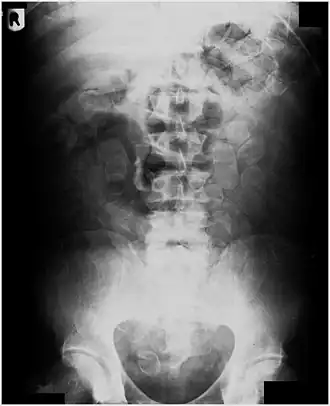

Bij oraal gebruik worden de bolletjes in hun geheel een voor een ingeslikt, samen met iets eetbaars of drinkbaars dat als glijmiddel dienstdoet. Dit eten of drinken mag niet te veel olie bevatten, omdat dit het rubber aantast. Normaliter slikken drugskoeriers tussen de 90 en 120 capsules met verdovende middelen. Blijkbaar krijgen ze wel van tevoren een licht dieet, om te voorkomen dat ze onverhoeds een aanval van diarree krijgen waardoor de drugs in een vliegtuigtoilet eindigen. Ook worden ze vaginaal of rectaal ingebracht. Na de vlucht kunnen de bolletjes weer uit de vagina of het maag-darmkanaal worden gehaald, al dan niet met behulp van laxeermiddelen.

De detentiecel is voorzien van een speciaal toilet, waarmee ontlasting kan worden vastgehouden en onderzocht op drugscapsules. Men kan dit voorkomen door in te stemmen met een bodyscan: deze kan aantonen of er wel of geen bolletjes zijn.

Deze manier van smokkelen is zeer gevaarlijk. Het menselijk maag-darmkanaal zit vol agressieve chemicaliën die de bolletjes kunnen aantasten. Ook vet en olie kunnen het rubber aantasten. Hierdoor, of door te haastig dichtmaken, kunnen bolletjes makkelijk knappen. Hoe klein ze ook zijn, ze bevatten meer dan genoeg drugs om de koerier aan een overdosis te laten overlijden. Een ander risico is dat de bolletjes het spijsverteringskanaal kunnen blokkeren (ileus). Bij ontdekking wordt de koerier dan ook door de overheid gedwongen van de drugs ontdaan, tevens voor diens eigen veiligheid. Dit gebeurt door de bolletjes operatief te laten verwijderen in het ziekenhuis.